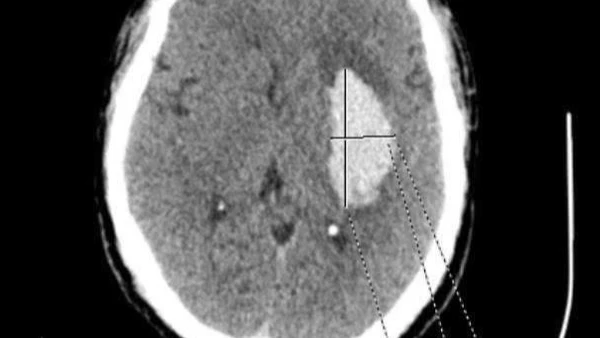

Ông N.V.X (68 tuổi, Vĩnh Phúc) đi khám chuyên khoa tiêu hoá vì cảm thấy đau bụng quanh rốn. Người bệnh đã được các bác sĩ đã tiến hành thăm khám, thực hiện các chỉ định cận lâm sàng và phát hiện bị phình hình thoi động mạch chủ bụng dưới thận.

ThS Khổng Tiến Bình, Trưởng khoa Nội, Can thiệp Tim mạch - Hô hấp, Trung tâm Tim mạch và Lồng ngực, Bệnh viện Hữu nghị Việt Đức cho biết, người bệnh được chẩn đoán phình động mạch khi có sự phình khu trú động mạch với đường kính ngang lớn hơn 1,5 lần kích thước động mạch bình thường. Phình động mạch chủ dẫn đến nhiều biến chứng nghiêm trọng như: Phình tách hoặc vỡ động mạch. Đa số các trường hợp phình đồng mạch chủ là do tăng huyết áp do đó với người phình động mạch chủ, kiểm soát huyết áp là điều cực kỳ quan trọng để không xảy ra những biến chứng nguy hiểm.

Ngay khi nhập viện, chỉ số huyết áp đo được trung bình sau ba lần của người bệnh là 150/90mmHg. Ông X đã được đo huyết áp thường xuyên và ghi holter huyết áp để loại trừ người bệnh tăng huyết áp do tâm lý khi tiếp xúc với nhân viên y tế (tăng huyết áp áo choàng trắng) và kết quả ông bị tăng huyết áp độ II. Bên cạnh bệnh phình động mạch chủ bụng, khi siêu âm tim các bác sĩ phát hiện ông X bị giãn động mạch chủ ngực - một hậu quả nữa do căn bệnh tăng huyết áp của ông.

Hiện tại, ông Q đang được điều trị tại khoa Nội, Can thiệp Tim mạch - Hô hấp, Trung tâm Tim mạch và Lồng ngực, Bệnh viện Hữu nghị Việt Đức. Ông được theo dõi và kiểm tra toàn bộ hệ cơ quan trong cơ thể, trong đó có mạch vành là mạch máu nuôi tim. Kết quả ông Q có tổn thương hẹp 60-70% 2/3 nhánh động mạch vành.

Như vậy, người bệnh vào viện vì cơn đau ngực sau đó tìm thấy tổn thương động mạch cả ở bụng và ngực. Cả hai tổn thương này đều là những tổn thương rất nguy hiểm và trong trường hợp của ông Q đó là hậu quả của tăng huyết áp không được điều trị.